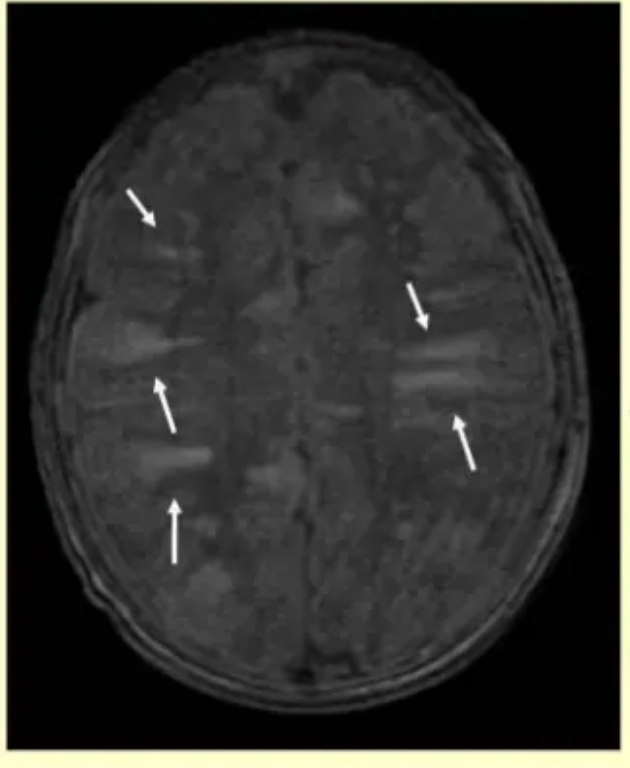

Lack of Myelination in the Anterior Limbs of the Internal Capsule Associated with Cri-du-Chat Syndrome: Case Report

H. Lee, S. You, +1 author Hyun-Hae Cho

Published 2015

Medicine

Investigative Magnetic Resonance Imaging

A 21-month-old girl with cri-du-chat syndrome in conjunction with developmental delay underwent brain magnetic resonance imaging (MRI). The MRI showed hypoplasia of the brain stem, a normal cerebellum, thinning of the corpus callosum, and a lack of myelination in both anterior limbs of the internal capsule. She also had neonatal bilateral subependymal cysts. We believe that the symmetrical lack of myelination in both anterior limbs of the internal capsule could be a diagnostic clue of cri-du-chat syndrome. LESS